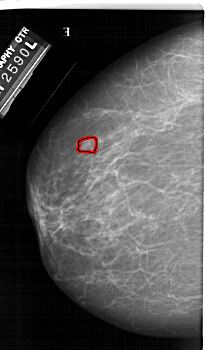

A_1423_1.LEFT_MLO

LEFT_MLO LINES 6871 PIXELS_PER_LINE 4096 BITS_PER_PIXEL 12 RESOLUTION 43.5 OVERLAY

FILE: A_1423_1.LEFT_MLO.OVERLAY

TOTAL_ABNORMALITIES 1

ABNORMALITY 1

LESION_TYPE MASS SHAPE LOBULATED MARGINS CIRCUMSCRIBED

ASSESSMENT 4

SUBTLETY 3

PATHOLOGY BENIGN

TOTAL_OUTLINES 1

BOUNDARY